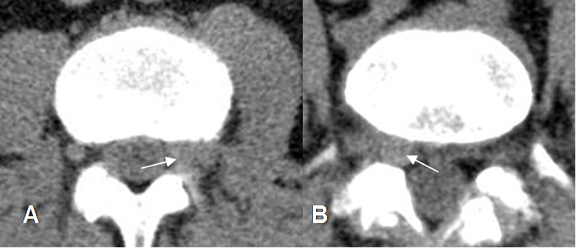

Fig 86. Hernia de disco.

A: TAC axial y B: RM axial en T1. Prominencia asimétrica en contacto con el saco dural, borra la grasa epidural y comprime la raíz, que corresponde a protrusión.